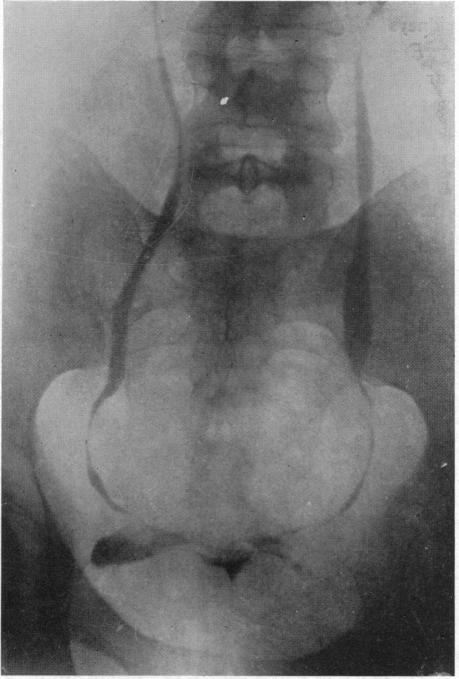

STRICTURE OF THE URETER.

Ann Surg. 1925 Apr;81(4):839-50. doi: 10.1097/00000658-192504000-00013.